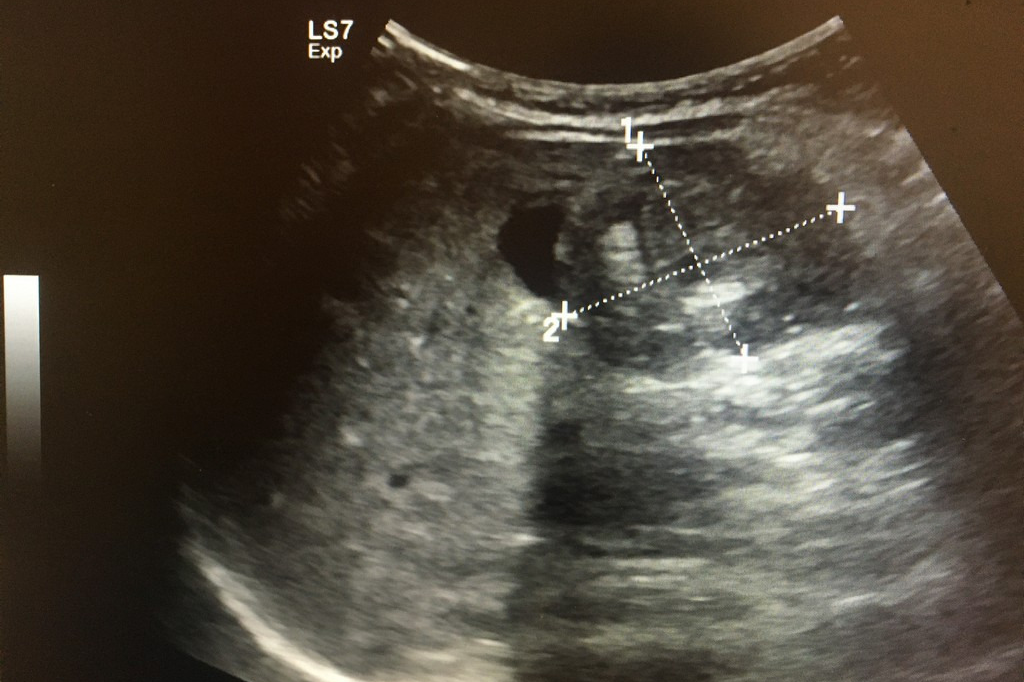

복부 초음파 검사는 인체의 복부 내 장기들을 실시간으로 확인할 수 있는 비침습적 영상 진단 방법입니다. 고주파 음파를 복부 피부에 쏘아 내부 장기의 반사 신호를 영상화하는 기술로, 내시경이나 CT와는 달리 방사선 노출 없이 안전하게 검사할 수 있다는 장점이 있습니다.

간(Liver)

- 지방간

- 간경화

- 간암(간세포암, 전이성 암)

- 간낭종

- 간혈관종

복부 초음파로 조기 발견 가능한 주요 암

복부 초음파는 다음과 같은 암의 조기 진단에도 큰 역할을 합니다.

- 간암: 특히 간경화 및 B형/C형 간염 환자에 중요